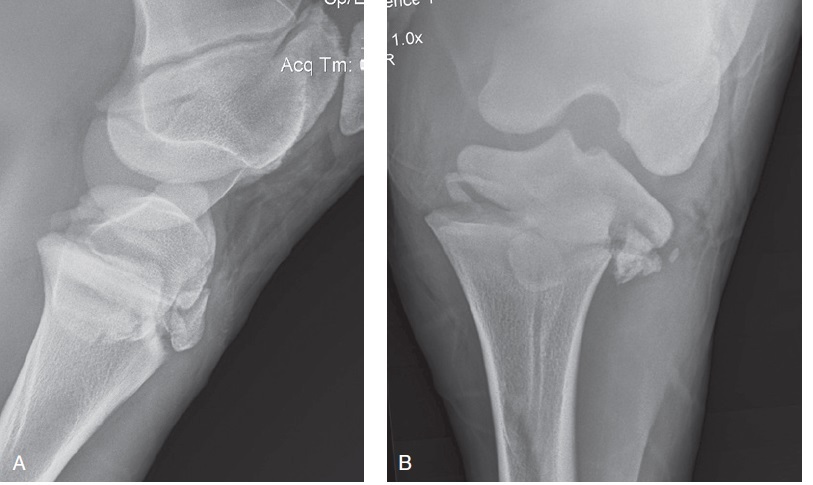

Figure 100-8. Lateromedial (A) and caudocranial (B) radiographic views of a spiral comminuted displaced midshaft tibial fracture in an adult horse.

Figure 100-8. Lateromedial (A) and caudocranial (B) radiographic views of a spiral comminuted displaced midshaft tibial fracture in an adult horse. Caudocranial (C) and lateromedial (D) radiographic views of the repaired fracture using two interfragmentary 4.5-mm cortex screws inserted in lag fashion and two staggered broad 4.5-mm DCPs, 3 weeks after surgery.